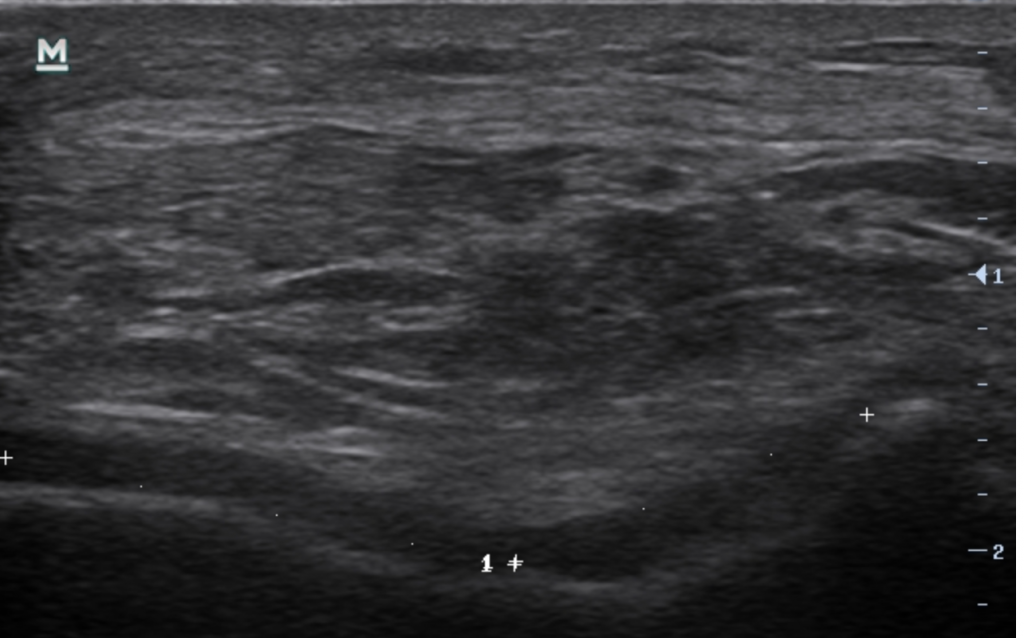

Tous signes de gravité ont pu être éliminés, mais pour comprendre avec précision la pathologie du patient, une  échographie est prescrite.

L’échographie démontre bien un problème entre le fémur et la rotule: une arthrose fémoro-patellaire.